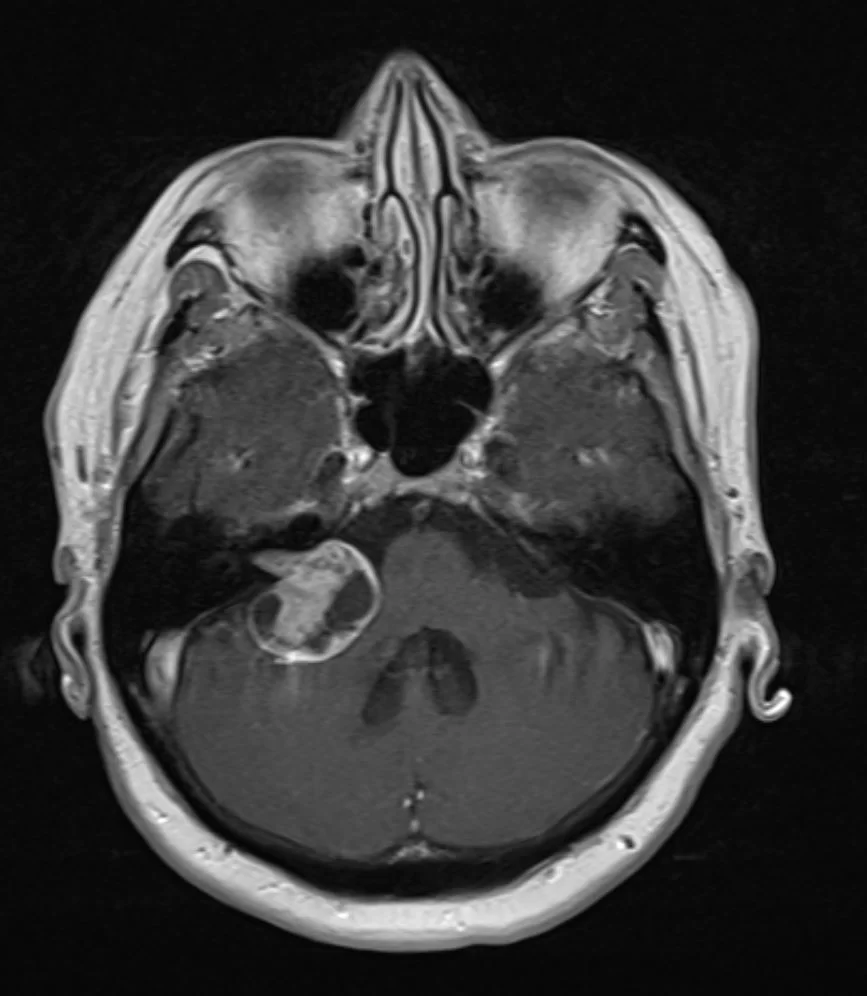

Μηνιγγίωμα γεφυροπαρεγκεφαλιδικής γωνίας δεξιά

Ασθενής άνδρας, 45 ετών με αιμωδίες του δεξιού ημιπροσώπου, ιλίγγους και κεφαλαλγία. Η μαγνητική τομογραφία εγκεφάλου ανέδειξε εκτεταμένη χωροκατακτητική εξεργασία